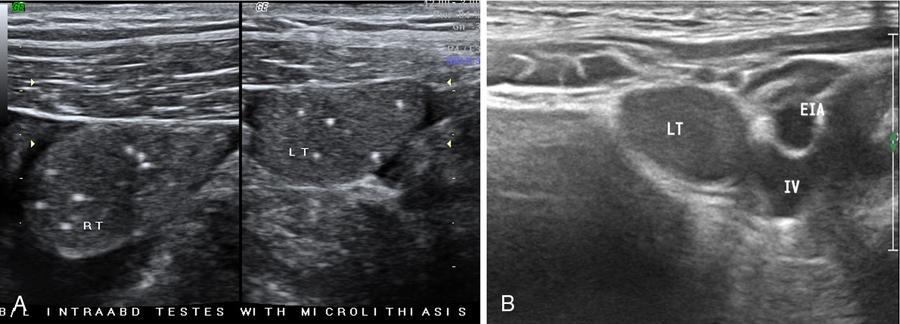

Fig. 11.8.6(A) Suprapubic US scan of a 22-year-old male with empty scrotal sac shows bilateral small-sized intraabdominal UDT with microlithiasis. (B) Another case showing intraabdominal undescended left testis (LT) adjacent and medial to iliac vessels and abutting urinary bladder wall.

Visibility of nonpalpable intraabdominally located testis is impaired by bowel gases at US, however, with experienced hands the same can be depicted on ultrasound deep to internal inguinal ring, adjacent to iliac vessels and lateral bladder wall. Tracking the cord technique is also a valuable sign in localizing nonpalpable testis (also ectopic testis) (Fig. 11.8.3).